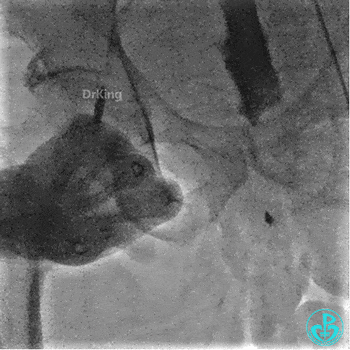

左股入路JR 4.0指引导管翻山造影,右侧股动脉穿刺点局部造影剂外漏。

翻山5.0×8mm球囊局部封堵破口处加术者用手局部压迫。

球囊封堵30分钟后造影,破口局部无渗漏,下台观察。